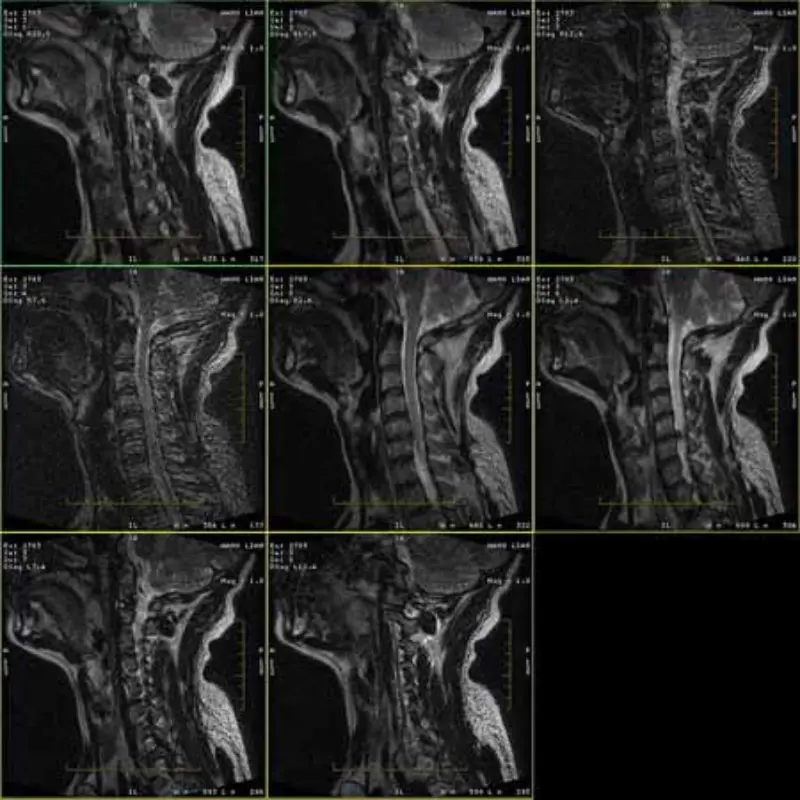

FRFSE आणि GRE प्रोटोकॉलच्या प्रतिमांमध्ये भूत असते आणि कधीकधी कमी SNR प्रतिमा एका मालिकेत दिसतात. परंतु SE प्रोटोकॉल प्रतिमा सामान्य आहेत.

कृपया संलग्न प्रतिमा पहा.